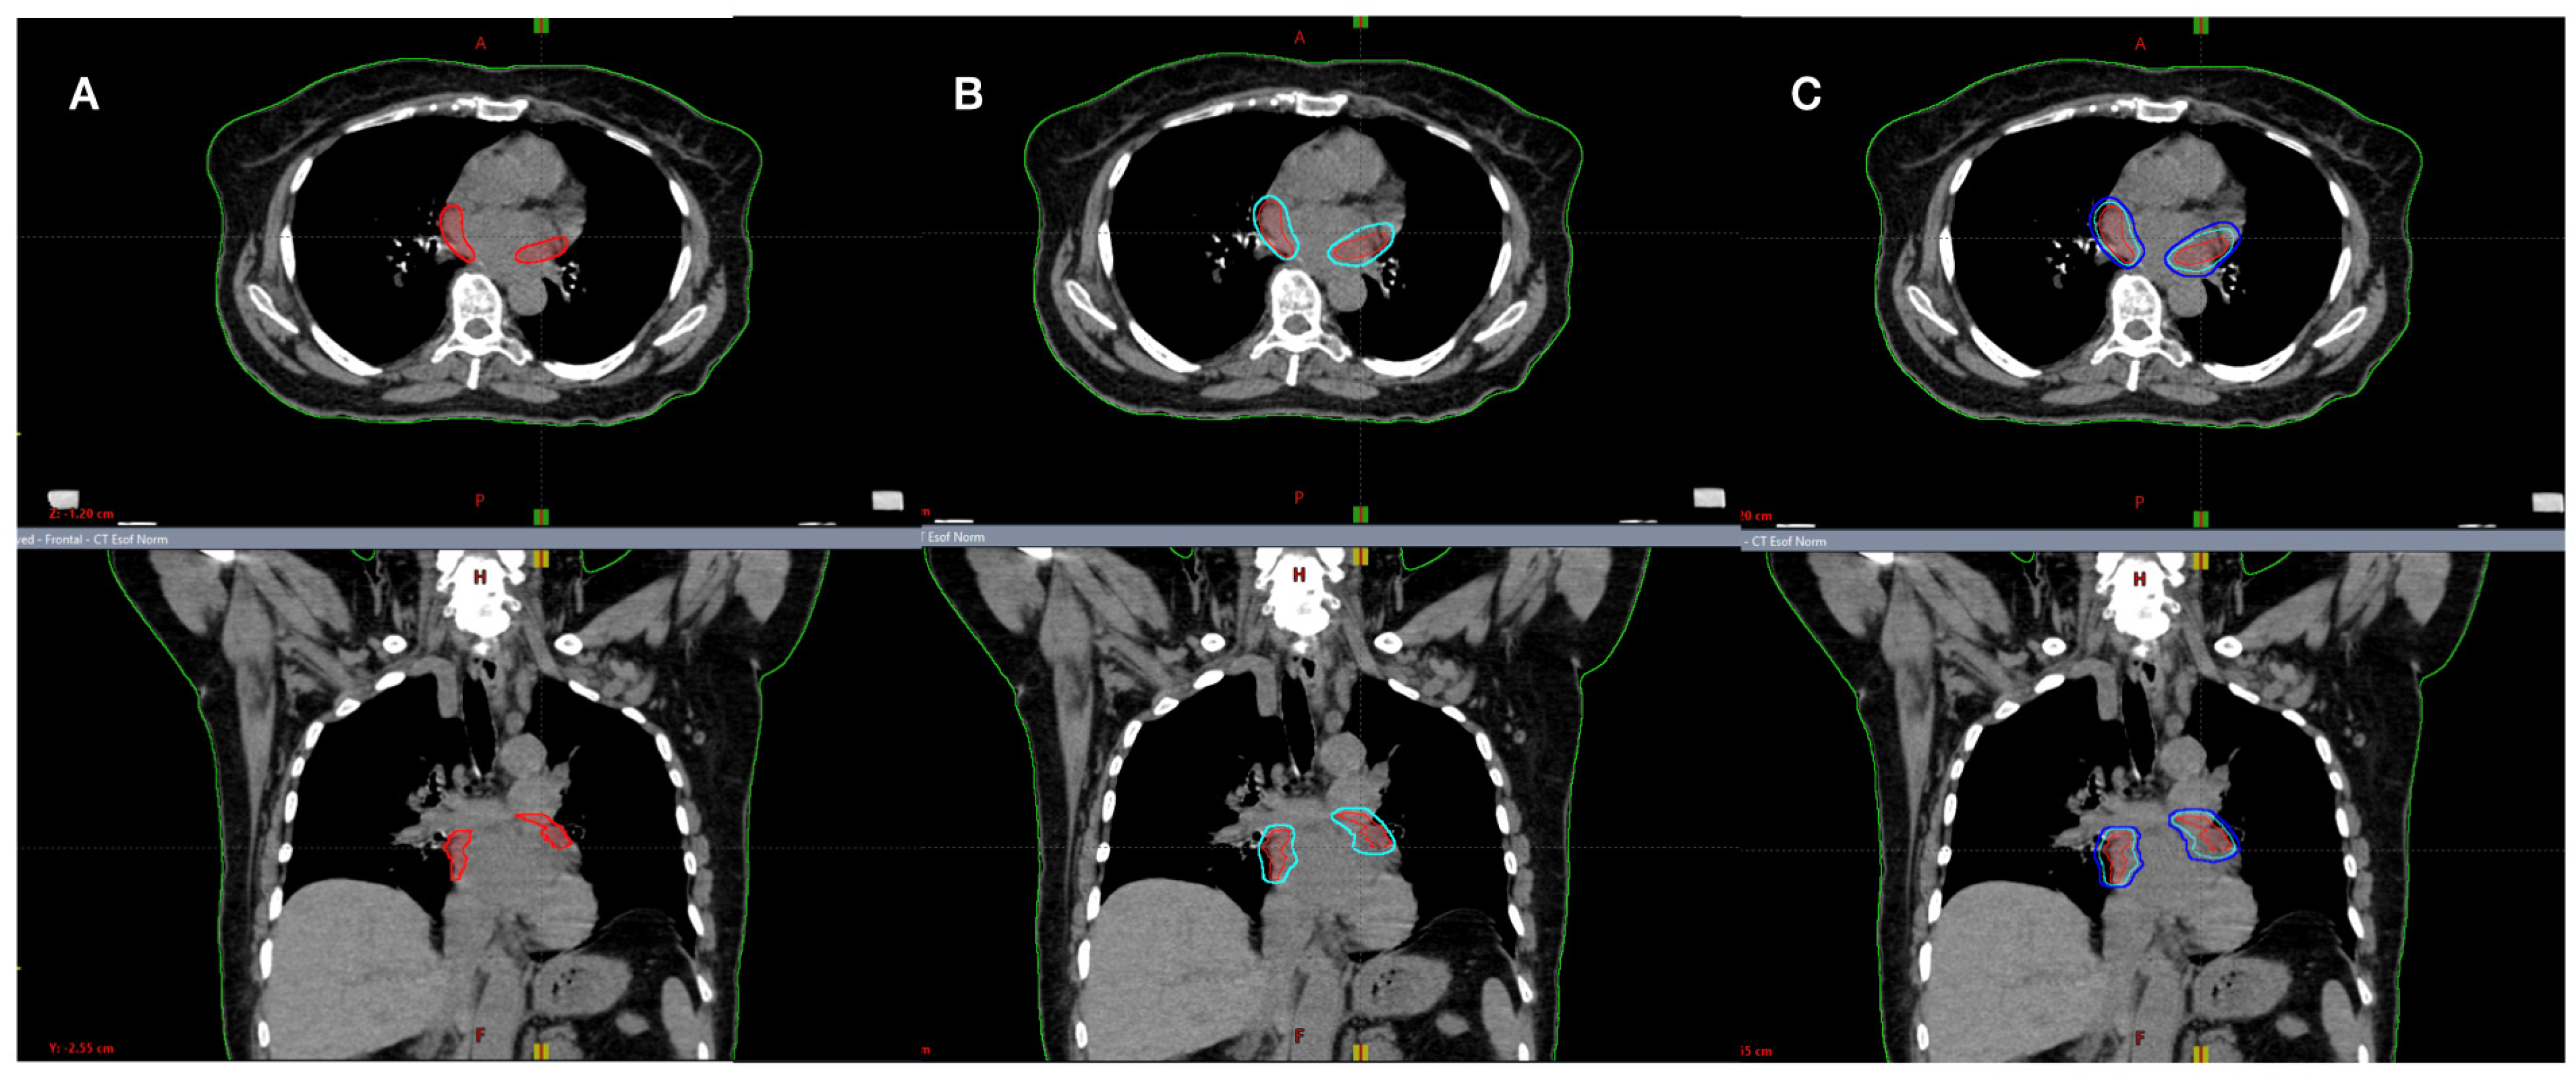

The clinical target volume (CTV) was identified in accordance with radiation oncology and cardiology, considering the area around PVs, based on anatomical CT imaging, and generating 2 separate target volumes: one around the left PVs (CTVleft) and the other on the right PVs (CTVright).

Based on 4D-CT acquisition, an internal target volume (ITV) was added to CTVs in order to compensate for respiratory motion. Although the CT scan was not synchronized to the electrocardiogram (ECG), the magnitude of ITV was adequate to also include heart displacements [15]. Finally, the planning target volume (PTV) was defined by adding 0–2 mm to the ITV, excluding the overlap area with OaRs/PRV, where PTV was cropped (Figure 1 and Figure 2).

Figure 1.

Definition of (A) clinical target volume (CTV); (B) internal target volume (ITV); (C) planning target volume (PTV).

Since there are no other analyses in the literature about the use of LINAC for AF-STAR, we could only compare these results with a few published cases performed with a different technology (Cyberknife) [18,19]. As previously reported, the target definition was not the same. In the Cyberknife cases, the PVs and the left atrial posterior wall were irradiated. The mainstay AF ablation approach is PVs isolation, while appropriate/effective ablation targets, including the atrial wall, remain poorly defined [1,18,19]. Thus, in the present trial, the target was defined as the area around the PVs, defined by radiation oncology and cardiology (Figure 1 and Figure 2). In fact, the present mean CTV was 23 cc, while for Cyberknife, data is roundly 50 cc for all cases.